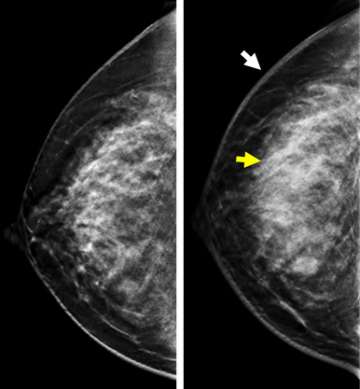

Case: Inflammatory Breast Cancer Figure 1

Figure 1. Screening mammogram image of the right breast one year before (left) and diagnostic mammogram images at the time of presentation with symptoms of IBC (right). Compared to one year prior, there is moderate skin thickening (white arrow) and increased density of the breast tissue (yellow arrow). Hypoechoic areas were noted on screening ultrasound (not shown).